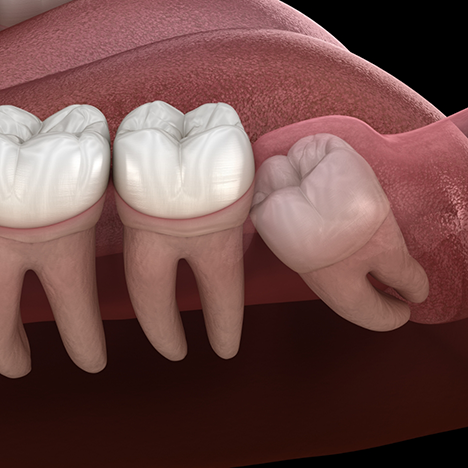

- One or more wisdom teeth might not have the space to emerge, which is called a partial eruption. This can lead to a serious infection that may compromise your gums or other teeth.

- If wisdom teeth grow at an awkward angle, they can push against other teeth. Your bite may become misaligned, and pain and swelling may develop.